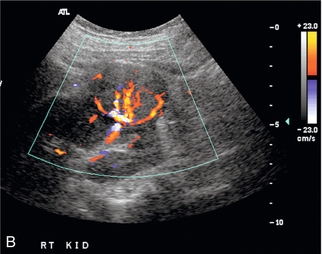

Артериовенозная фистула в нативной почке встречается редко, за исключением случаев предшествующей биопсии почки, и ее нельзя заподозрить при сонографии, если не проводится цветная или энергетическая допплерография. Цветной или энергетический допплер обычно показывает большое извилистое скопление сосудов. Спектральные допплеровские сигналы почечных артерий, питающих фистулу, покажут высокую скорость и низкое сопротивление ( рис. 9-19 ). Основная почечная вена может быть расширена, а в венах вблизи фистулы могут обнаруживаться артериализованные волны ( рис. 9-20 ).